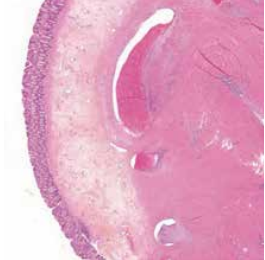

Les atteintes colo-rectales sont les lésions les plus fréquentes de l’endométriose digestive (> 90 %), suivies de loin par les atteintes iléo-caecales (10 %). Elles sont isolées dans la moitié des cas, et qualifiées de multifocales lorsque les atteintes secondaires sont distantes de moins de 2 cm du nodule principal, ou multicentriques si elles en sont éloignées de plus de 2 cm (5). Au plan anatomopathologique, l’endométriose colo-rectale se traduit par la présence de structures glandulaires endométriales cernées de chorion cytogène. Les glandes contiennent des microhémorragies qui, au fil des cycles menstruels, induisent la formation de microkystes entourés d’histiocytes, d’une hyperplasie des faisceaux musculaires, et d’une fibrose collagène, cette dernière, fréquente, conduisant à accentuer les remaniements anatomiques (figure 1). L’aspect histologique de l’endométriose profonde diffère de celui de l’endométriose péritonéale et ovarienne par le fait que le type glandulaire peu différencié y est plus fréquent ; ces atypies épithéliales pourraient résulter d’une absence de régulation par les facteurs suppresseurs du liquide péritonéal (6). La progression de l’atteinte colo-rectale se fait de manière centripète, entraînant l’infiltration successive des différentes tuniques de la paroi digestive jusqu’à la muqueuse dans les formes « traversantes ». En 2011, dans une revue de la littérature portant sur 49 études évaluant des patientes opérées (7), les atteintes pariétales ont été inventoriées comme suit : séreuse (95 %), musculeuse (95 %), sous-muqueuse (38 %) et muqueuse (6 %).

Figure 1 : Infiltration musculeuse par de l’endomètre fonctionnel